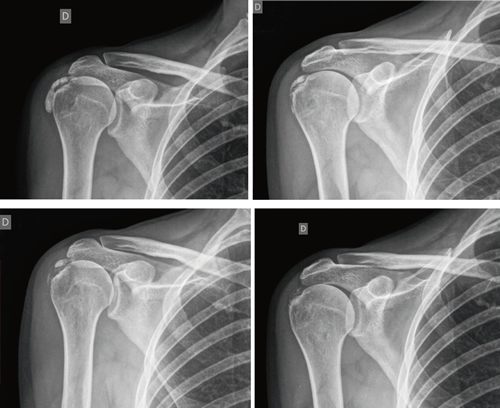

Figure 1

Results: Mean age 54.6 years (n = 138). Female (73.1 %; n = 101); female to male ratio 3:1. Supraspinatus tendon (94.6 %; n = 124), subscapularis (5.4 %; n=14); left shoulder (55.1 %; n = 76), right shoulder (44.9 %; n = 62). Bilateral 1.4 % (n = 2). Right handed 96.3 % (n = 133); Personal history: smoking (19.5 %; n = 27), diabetes (7.2 %; n = 10); disease time averaged 6.08 months; acute-subacute pain (less than 3 months) 47.1; (n = 65), chronic pain (greater than 3 months) 52.9 % (n = 73). Radiological type: formative 75.3 % (n = 104); resorptive 24.7 % (n = 34). Average number of sessions: 20.5. Treatment complications 2.8 % (n = 4): intolerance/erythema/burn. Occupation: administrative 39.8 % (n = 55), manual jobs 60.2 % (n = 83).